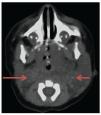

Laboratory studies, blood count, blood chemistry, blood gases and karyotype were normal. Computed axial tomography of the lateral neck showed clear asymmetry in volume with a left predominance at the expense of a hypodense, ill-defined image with apparent liquid attenuation. Vascular structures were shifted medially and later, anterior to the sternocleidomastoid muscle. In this image we observed parapharyngeal fat displacing the air space to the right. Compression and conditioning gauge decreased >50% (Fig. 2).

Figure 2 Computed axial tomography of the head and neck. Increased volume of the neck is observed predominantly on the left that displaces medial and posterior (arrows) vessels, anterior to the sternocleidomastoid muscle, with linear vascular hyperdense images in the interior. Reinforcement is not identified after administration of contrast medium.